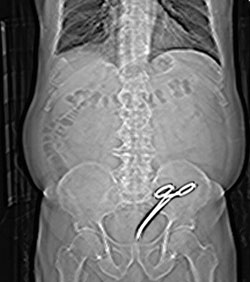

Ослушавшись советов, в соседнем Краматорске пенсионеру сделали томографию. То, что увидели на снимке, ошарашило весь персонал больницы. У мужчины в животе находился 16-сантиметровый медицинский зажим.